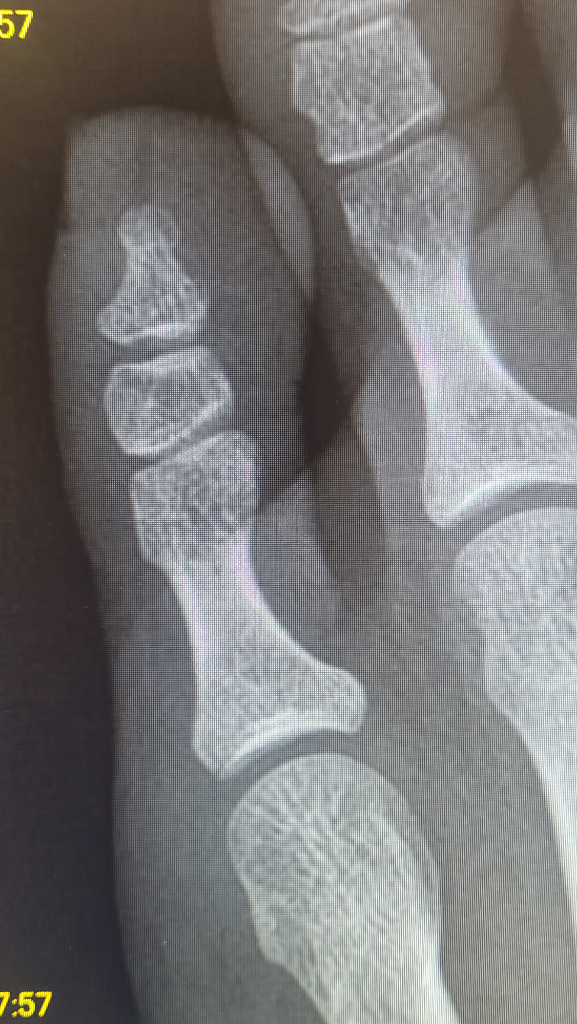

3월5일에 왼쪽 새끼발가락을 다쳐서 3월6일에 5족지 근위지골 골절을 진단 받았습니다.

당시 의사선생님께서 엑스레이상 골절 의심부위도 보여주셨구요.

오늘 찍은 엑스레이에선 눈을 씻고 찾아봐도 골절로 의심되는 부분이 안 보이는데 이럴 수도 있는걸까요?

• 1번 째 사진

• 2번 째 사진

• 올리신 엑스레이 사진을 통해서 보았을 때에는 골절 부위가 명확하게 보이지는 않습니다. 이전에 보였던 골절 소견이 애매하게 보여서 골절 같아 보였을 수도 있어 보입니다. 보통 골절이 2주 만에 눈에 씻은 듯이 사라지지는 않습니다.